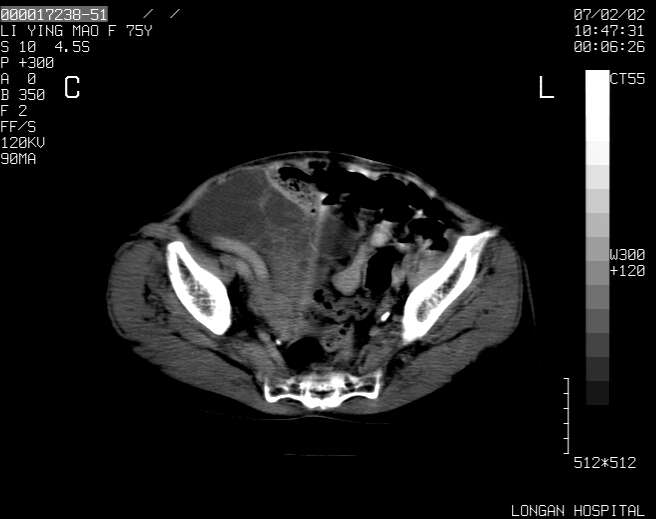

以下是引用dyqct在2007-2-10 8:53:00的发言:[br]考虑:1、肝脏多发囊肿[br] 2、左肾囊肿,右肾多发结石并积水。[br] 3、右胸少量积液。[br] 4、右肾周包裹性积液或淋巴管瘤(有见缝就钻的征象、薄隔、小结节状钙化)?[br] 5、腰椎动脉瘤样骨囊肿?[br] [br] [br]